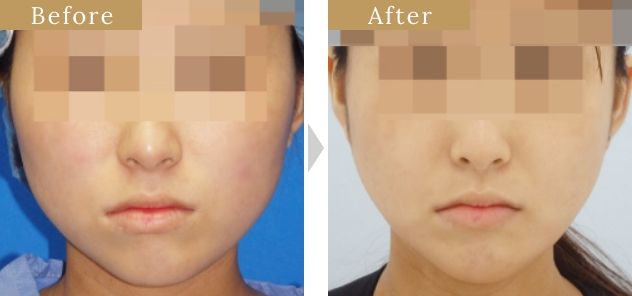

症例

『下顎角形成骨切り術』の

特徴

骨切り量が非常に大きい

オトガイ神経を剥離して下顎骨を広範囲に露出し、神経の上下からアプローチするため、骨切り範囲がオトガイ部先端から下顎角直前におよび、切除幅8㎝~10㎝、全長14cm~16cmと非常に大きい。

スムーズなカーブを描く

骨切りが可能

骨切りカッターを骨面に垂直に当てることが出来るため、スムーズで自然なカーブを形成出来る。

左右差が少ない

術者の利き手に影響されないため左右対称に骨切り出来る。

安全性が非常に高い

顔面神経・顔面動脈とは離れた位置での操作であることと、下顎角裏側の翼突筋群を十分に剥離することが出来るため、安全性が非常に高い。また、手術中に透明3-D立体模型にて下歯槽神経管の位置を確認しながら骨切りするため、下歯槽神経を損傷する可能性が殆どない。

腫れが非常に少ない

骨切り部分のみを剥離するため腫れが最小限に抑えられる。